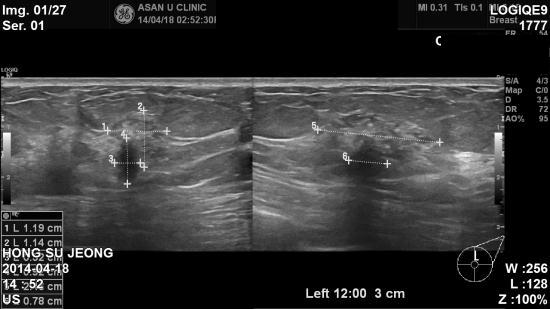

본원 초음파상 좌측유방 11:30분방향, 12시방향, 2시방향에

악성으로 의심되는 종괴소견있어 조직검사결과

상피내암 및 침윤성 유관암으로 진단되었습니다.

다행이 초음파상 겨드랑이 림프절 전이소견은 없었지만,